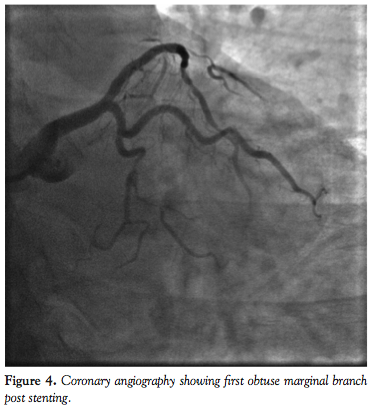

For the overall study group, there were no peri- or postprocedural MACEs. Mean fluoroscopic time was 25.3 ± 17.2 minutes and mean contrast volume was 203.1 ± 80.1 mL. Figures 1 through 8 illustrate our experiences with Integrity coronary stents in some of the “classical” tortuous coronary vessels.

One striking feature we observed about the Integrity coronary stent was that it conformed very well to the vessel wall (Figures 1-8). This is important, since it means the stent has sufficient radial strength to resist the elastic recoil of the media and can mold its shape along the contour of a curved segment with minimal vessel straightening and provide a large desired lumen. When the DES is implanted, excellent apposition of the struts on the vessel wall will ensure uniform delivery of the cytostatic drug to prevent neointimal hyperplasia. An in vitro conformability test15 has shown the Integrity DES to have better strut apposition and lower vessel wall stress when compared to other market-leading DESs. This has